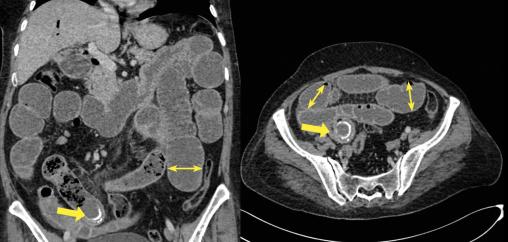

- une distension hydro-aérique de l’ensemble des anses grêliques en amont d’une formation arrondie bien limitée de densité calcique estimée à 700 UH, rappelant un calcul biliaire siégeant au niveau de l’avant-dernière anse iléale contrastant avec un aspect plat du reste du segment iléal et du côlon (fig. 1) ;